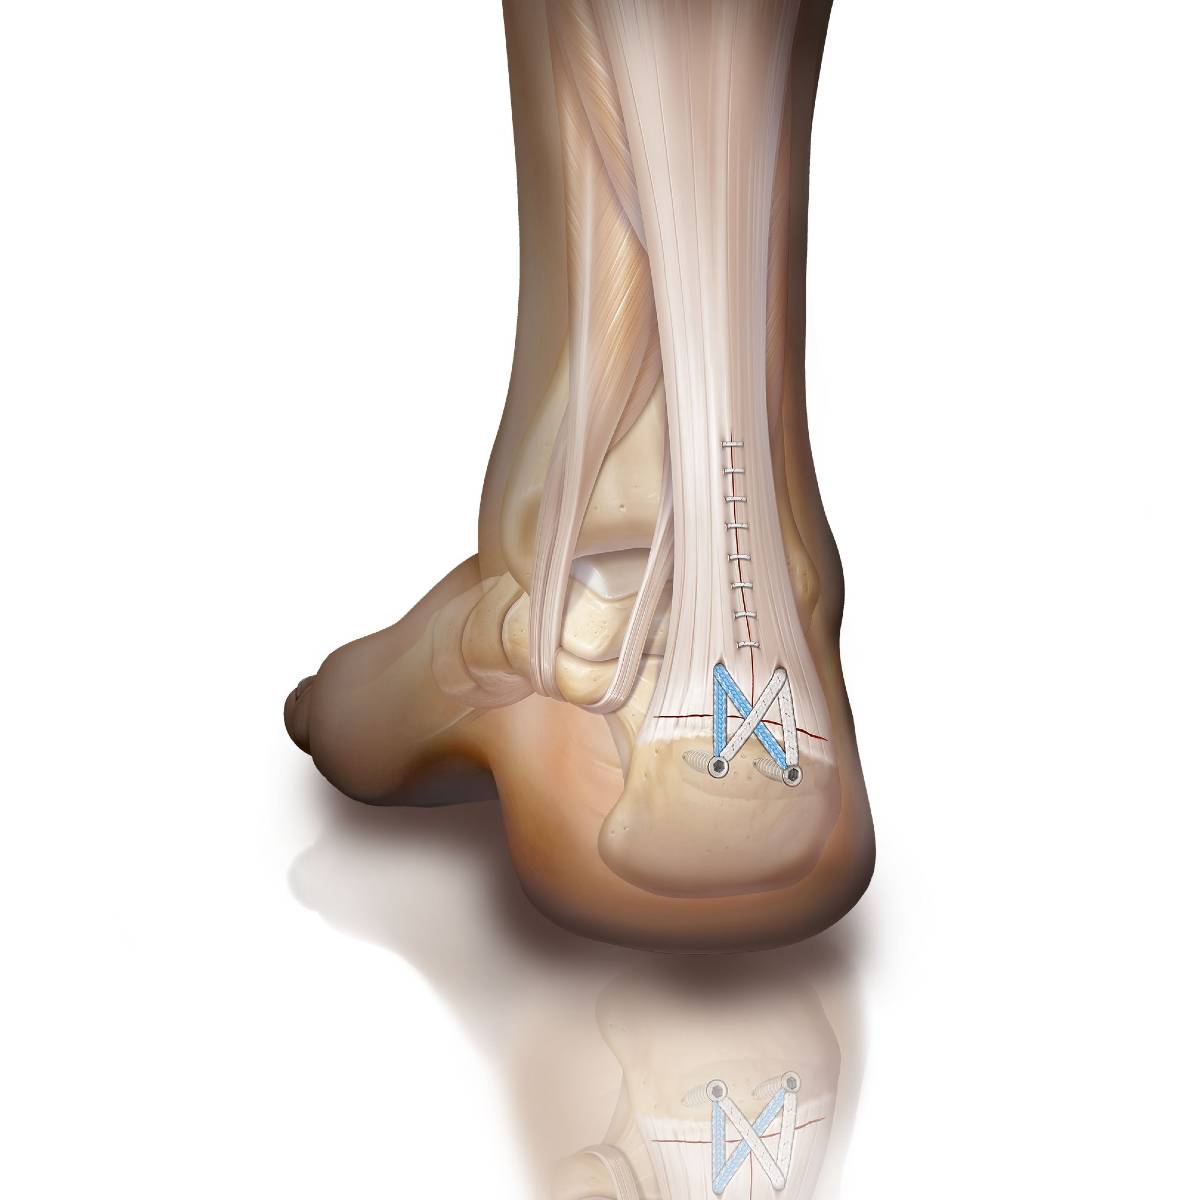

Réparation du tendon d’Achille – technique SpeedBridge®

Lorsque le tendon d’Achille est rompu près de son extrémité basse (extrémité distale) on peut le réinserer à son point d’insertion sur l’os du calcanéum.

- on incise longitudinalement l’extrémité inférieure du tendon d’Achille pour dégager l’os du calcanéum

- si nécessaire l’os est raboté (déformation d’ Haglund) pour préparer la mise en place des ancres

- on perce l’os afin de placer 2 ancres pour fixer les sutures

- les sutures sont passées dans l’extrémité distale tendon d’Achille

- on perce l’os juste en dessous du point d’insertion du tendon d’Achille afin de placer 2 ancres PushLock

- on tend les sutures afin de réaliser une solide fixation en forme de X

- on suture l’incision initiale

Cette technique Achilles SpeedBridge ™ avec 4 ancres de fixation offre une plus grande surface d’appui sur le calcanéum ce qui améliore la stabilité et permet une reprise précoce des activités courantes.

Avantages de la technique SpeedBridge®

- Réduit le risque de rerupture du tendon d’Achille

- Diminue les problèmes de cicatrisation

- Récupération plus rapide

- Hospitalisation ambulatoire

- Sortie le jour même en marchant (avec l’aide de béquilles et botte de marche)

- Suites opératoires plus simples

Illustration © Arthrex.com